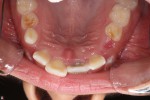

This is a 9yo girl with a high esthetic desire (wants to be a model/actor). She avulsed tooth #9 about 3 years ago, and she has been under treatment with other endodontists. I guess they attempted revascularization with MTA about year ago. #9 is ankylotic with a few mm’s infraposition. It is gray due to the MTA. #8 is slightly yellow/white due to calcification/obliteration but she says she feels cold testing and it is otherwise asymptomatic.

Then someone has to watch for her growth spurt – and as soon as it happens the tooth has to be removed – this will reduce the defect that will become much more on the growth of the maxilla – there is also some discussion about whether the ankylosed tooth will affect maxillary growth – this is much like placing an implant too early but worse. Orthodontic care for this potential movie star should also be delayed because any treatment now would have to be worked around this tooth and any eruptive force would created a vertical periodontal defect that might jeopardize the adjacent teeth.